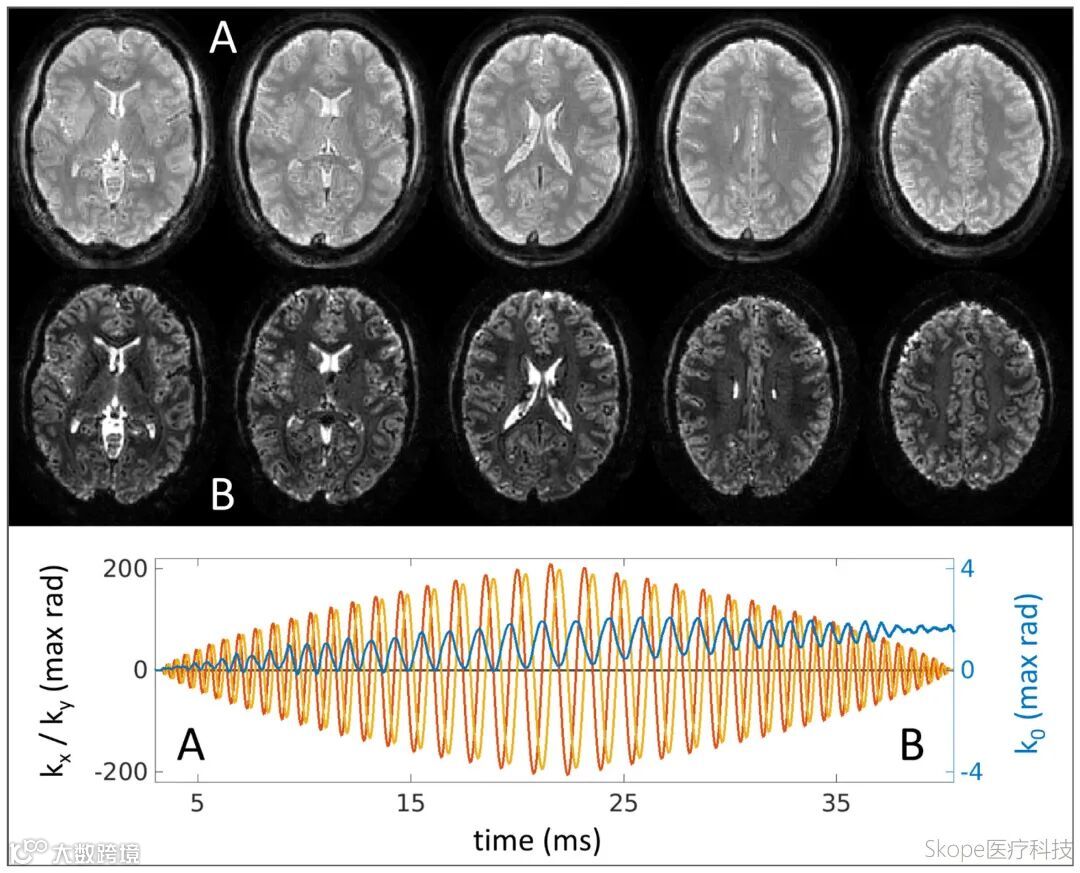

半激发(half-shot)螺旋采集展现多图像能力

spiral-in-out与out-in方案可在一次激发后获取两个不同TE下的图像,拓展了多对比采集可能性。实验证明,spiral-in-out在保持整体对比度的同时,能通过后段采集获取更清晰的脑脊液与白质边界;spiral-out-in则提供短TE与长TE图像对比,有助于脂肪抑制及结构保持,两者各具优势。

螺旋in out成像结果。每个切面两幅图像,脑脊液与白质边界更清晰。